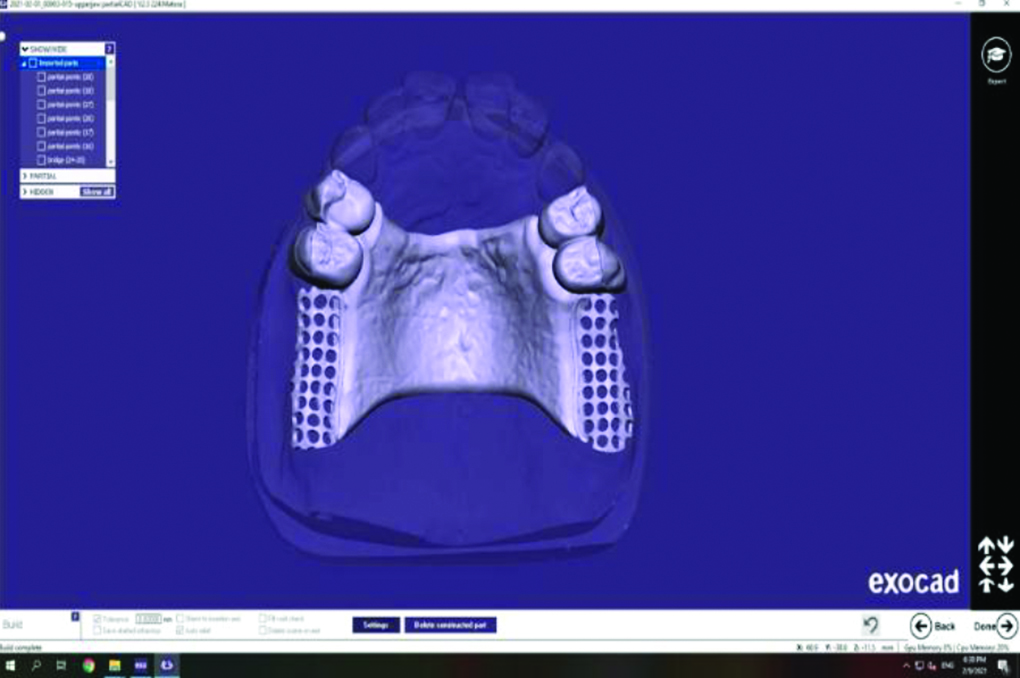

A gingivally trimmed master cast with removable dies was made from the duplication of the master cast. Then the gingivally trimmed cast, master cast, separate dies, and mounted casts were sprayed with a scanner spray (SCANTIST 3D Dental SCAN-SPRAY, scantist3d, Recklinghausen, Germany) and scanned with a desktop scanner (FREEDOM UHD, DOF, Seoul, Korea). The primary copings were designed with Exocad software (Exocad DentalCAD 2.4 Plovdiv, exocad GmbH, Darmstadt, Germany) to have a common path of insertion and their cervical third was made parallel, while the remaining occlusal was made conus with a 3-degree taper. The thickness of the copings was kept at the minimum thickness, which was 1 mm, with a 1-mm finish line, and the gap distance was set at 0.05 mm16 (Fig. 1).

Fig. 1: Designing of the primary copings with their cervical third was made parallel, while the remaining occlusal was made conus with a 3-degree taper using Exocad software

The mounted casts and the upper cast with primary copings were sprayed and scanned with the desktop scanner. The STL files were transferred to obtain a virtual model, which was digitally surveyed to determine the most acceptable path of insertion and to design secondary copings with a minimal axial and occlusal thickness of 1 mm and an occlusal space of 0.3 to 0.5 mm between the inner and outer crowns.24,25 A palatal plate major connector, denture base meshwork, and an external finish line were drawn26 (Fig. 2). The STL file of the designed secondary copings and RPD framework was transferred to the CAM software for preparation to be milled from PEKK (Pekkton®ivory, Cendres + Métaux SA, Biel/Bienne, Switzerland) or PEEK (ceramill® peek-AmannGirrbach AG, Koblach, Austria) blank according to the group (Fig. 3).

Fig. 2: Design of the double crown-retained RPD framework with palatal plate major connector using Exocad software